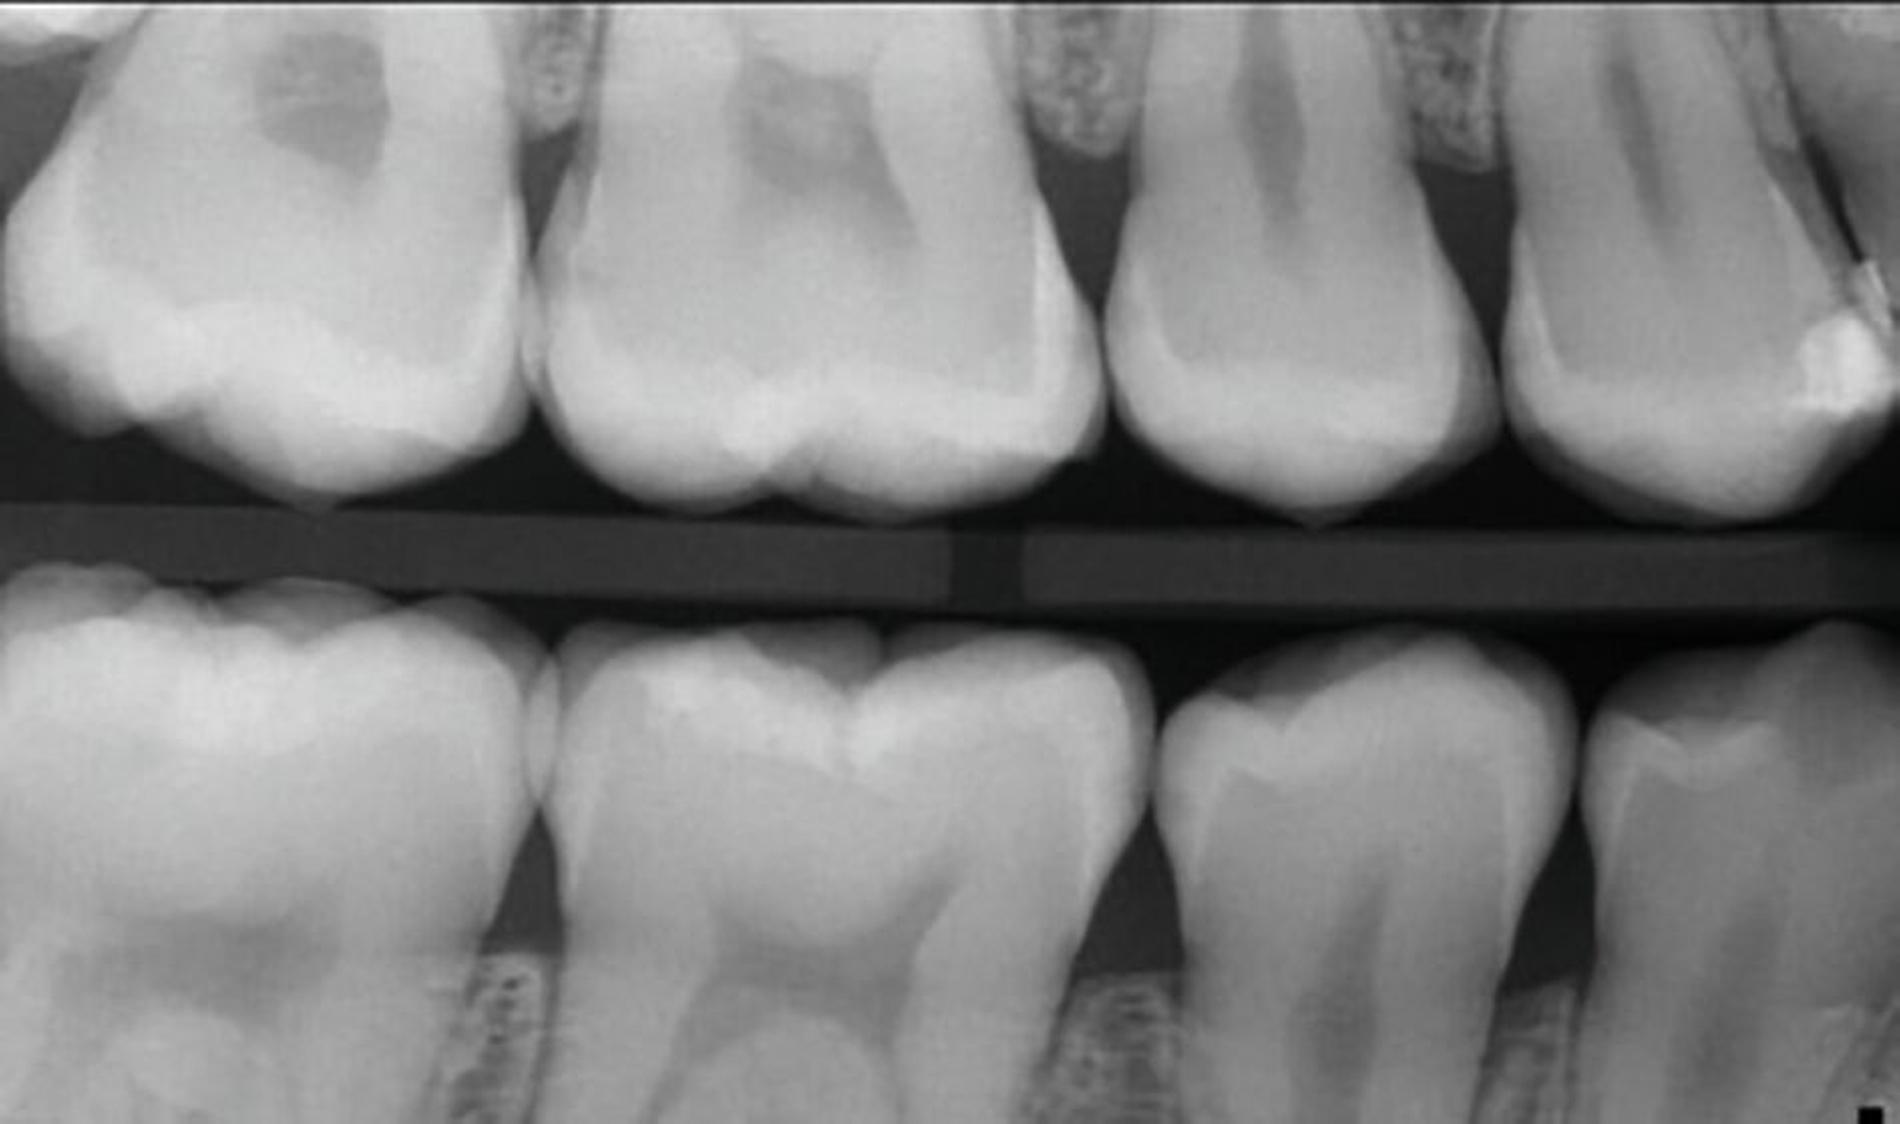

Der verkürzt dargestellte Patientenfall zeigt dieses minimalinvasive, innovative und kostengünstige Behandlungskonzept [Ahmed et al., 2023]. Im Kern werden dazu nach vorheriger Diagnostik orthodontische Separiergummis in die Zahnzwischenräume eingesetzt und für circa ein bis zwei Stunden in situ belassen. Direkt nach der Entfernung der Gummis erfolgt eine zügige, direkte klinische Untersuchung der Approximalkaries und eine Applikation von SDF zur Kariesinaktivierung mittels Microbrush.

Der Patientenfall belegt röntgenologisch die hohe Kariesaktivität vor der Behandlung, sowie die deutlich reduzierte Kariesaktivität nach der einmaligen SDF-Applikation in der oben genannten Technik nach knapp eineinhalb Jahren anhand von Bissflügelaufnahmen (Abbildungen 8a bis 8g). Eine retrospektive Pilot-Untersuchung an der Kinderzahnheilkunde in Greifswald gibt deutliche Hinweise auf die Wirksamkeit dieser Technik. Die Ergebnisse wurden beim diesjährigen Weltkarieskongress vorgestellt und diese Studie wurde ebenfalls von ORCA prämiert. Die Ergebnisse dieses Pilotprojekts zeigen für gut 90 Prozent der behandelten E1/E2/D1-Läsionen über einem Zeitraum von 15 Monaten keine weitere Progression in den Bissflügelaufnahmen [Ahmed et al., 2024].